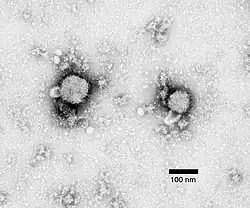

- Coronaviruses